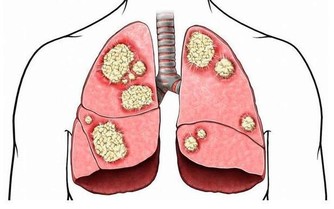

3.糖尿病並發症

濟南同濟吳峰醫生介紹說:對於糖尿病患者來講,當血糖升高時會引起神經纖維一系列的代謝紊亂,從而導致周圍神經病變。這時就會四肢末端麻木等。

一般來講,下肢會比上肢嚴重,如果患者已經知道自己患有糖尿病,應積極治療原發病。如果有糖尿病家族史、或肥胖,也應考慮糖尿病的可能。